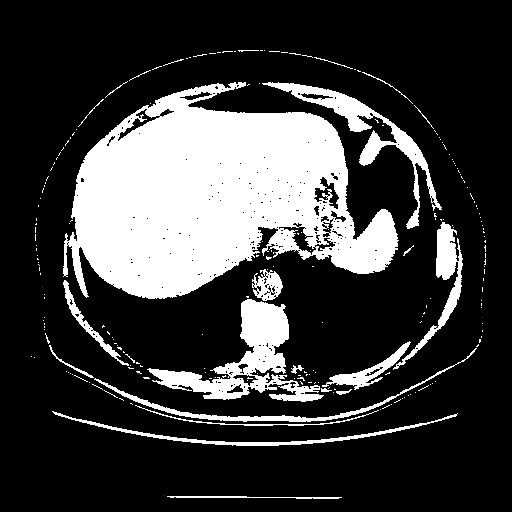

Generated VENOUS CT scan (A→B translation)

Full window (WL 1023.5, WW 4095 β†’ Low βˆ’1024, High +3071)

Actual HU range: [-1024.0, 3071.0]